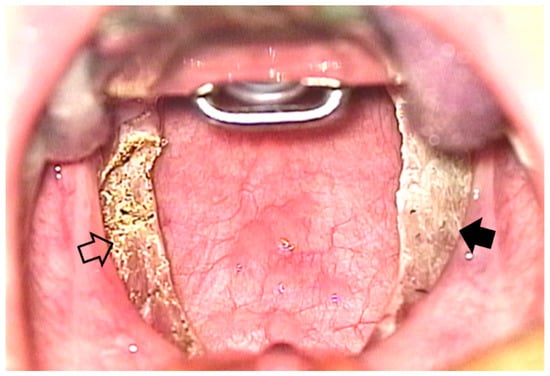

3. Results

3.2. Outcomes